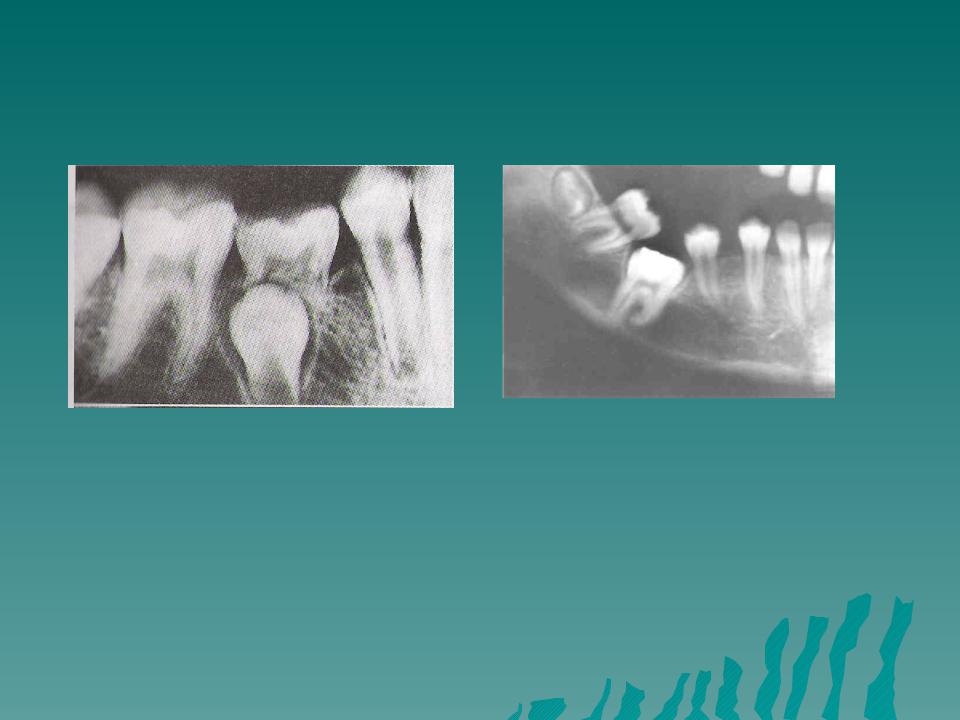

Ранняя и точная диагностика анкилоза является ключом к успешному лечению. Клинически анкилоз может проявляться задержкой прорезывания‚ неправильным положением зуба в зубном ряду‚ отсутствием физиологической подвижности и аномальным расположением соседних зубов. Однако‚ клиническая картина может быть не всегда явной‚ поэтому необходимы дополнительные методы исследования. Рентгенологическое исследование (ортопантомограмма‚ целевые снимки) позволяет визуализировать сращение корня зуба с костью и оценить степень анкилоза. Трехмерная компьютерная томография (КТ) дает более детальную информацию о структуре костной ткани и позволяет планировать хирургическое вмешательство с высокой точностью.

- Ортопантомограмма (ОПТГ)⁚ предоставляет обзорный снимок всей челюсти‚ позволяющий выявить анкилоз.

- Целевые рентгеновские снимки⁚ позволяют получить более детальное изображение анкилозированного зуба.

- Трехмерная компьютерная томография (КТ)⁚ обеспечивает точную визуализацию костной ткани и позволяет оценить степень сращения.